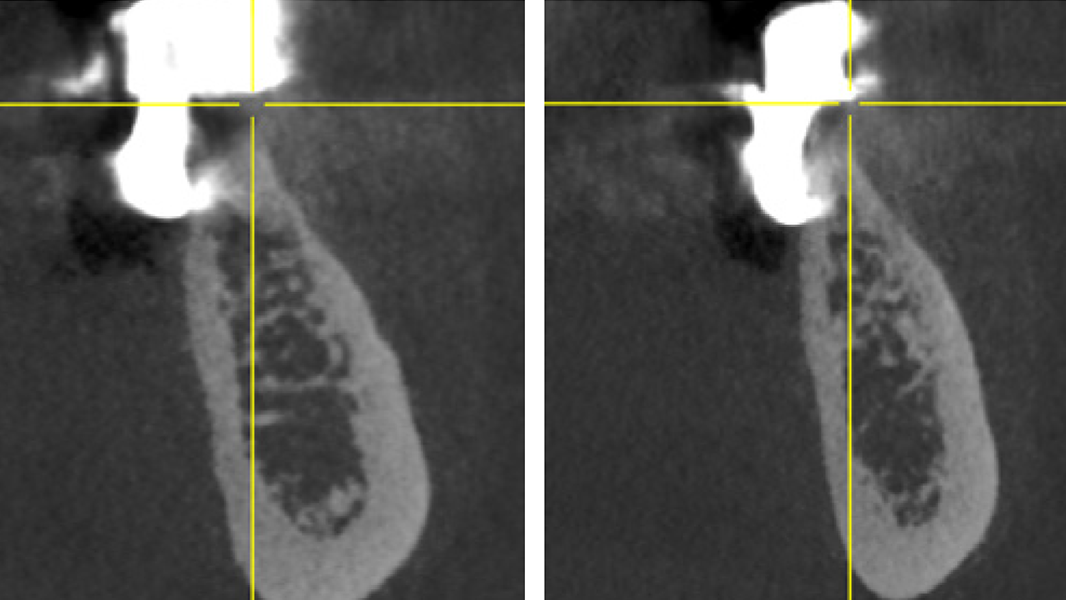

3 Kloss et al. Clin Case Rep. 2020, 8(5):886-893.

5 Kloss et al. Clin Oral Implants Res. 2018, 29, 1163.